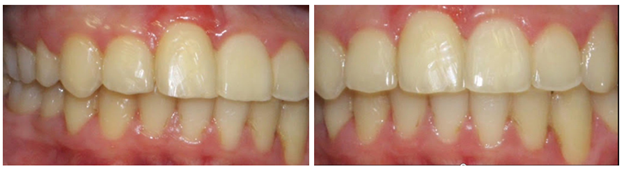

Figure 6 A&B In the event of excess overjet, maxillary Interproximal reduction (IPR) is used molar to molar following space closure to reduce the overbite/overjet relation to 1 to 3mm.

However, it is important to provide additional context regarding the initial treatment approach, which involved a gingival graft to address the periodontal dehiscence. However, by forgoing traditional periodontal treatment and opting for an orthodontic alveolar bone restoration protocol with FASTBRACES® Technologies, partial coverage of the exposed tooth by alveolar bone was achieved. This suggests the convergence and potential overlap between periodontics and orthodontic alveolar bone restoration, highlighting the need for interdisciplinary collaboration. A FASTBRACES® Technologies intervention restores alveolar bone architecture, naturally aligns the teeth thereby also altering the highly pathogenic microbial flora. This is because the universal constant is the alveolar bone clinical morphology with treatment directed towards the alveolar bone deficiencies when present. These four cases are successful examples of non- extraction orthodontic treatment with the patented systems of FASTBRACES® Technologies which appropriately address the relevant deficiencies in the alveolar bone clinical morphology while maintaining a 1 to 3mm overbite /overjet and not changing the patient’s natural molar relation. The authors believe the systems of FASTBRACES® Technologies induce alveolar bone remodeling by moving the tooth roots towards their natural properly erupted positions from the onset of treatment.